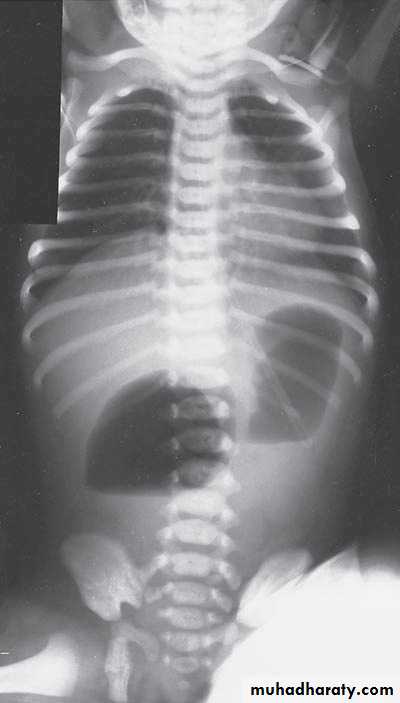

Scaphoid abdomen

Bowel Obstruction

N.E.C

Meconium ileus+atresia